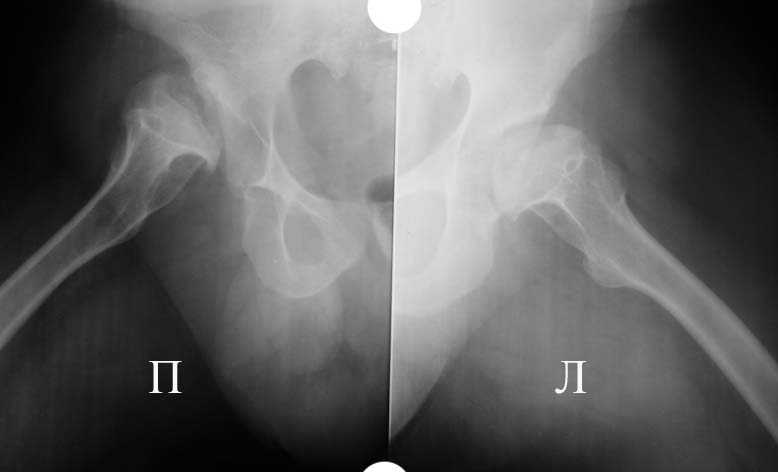

Прямая проекция т/б суставов

Вложение не в текстовом формате было извлечено…

Имя     : 1.jpg

Тип     : image/jpeg

Размер  : 24768 байтов

Описание: отсутствует

Url     : http://weborto.net:8080/pipermail/ortho/attachments/20090118/e452b84f/attachment-0003.jpg